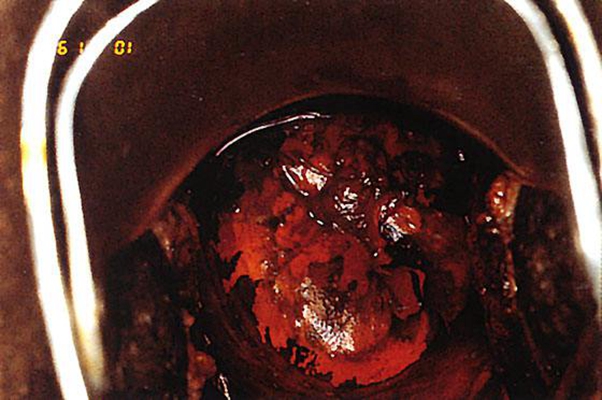

子宮頸癌圖片

宮頸癌

宮頸癌

宮頸癌

宮頸癌

宮頸癌

宮頸癌

宮頸癌

宮頸癌

宮頸癌

宮頸癌

宮頸癌

宮頸癌

宮頸癌

宮頸癌

宮頸癌

宮頸癌

宮頸癌

宮頸癌

宮頸癌

宮頸癌